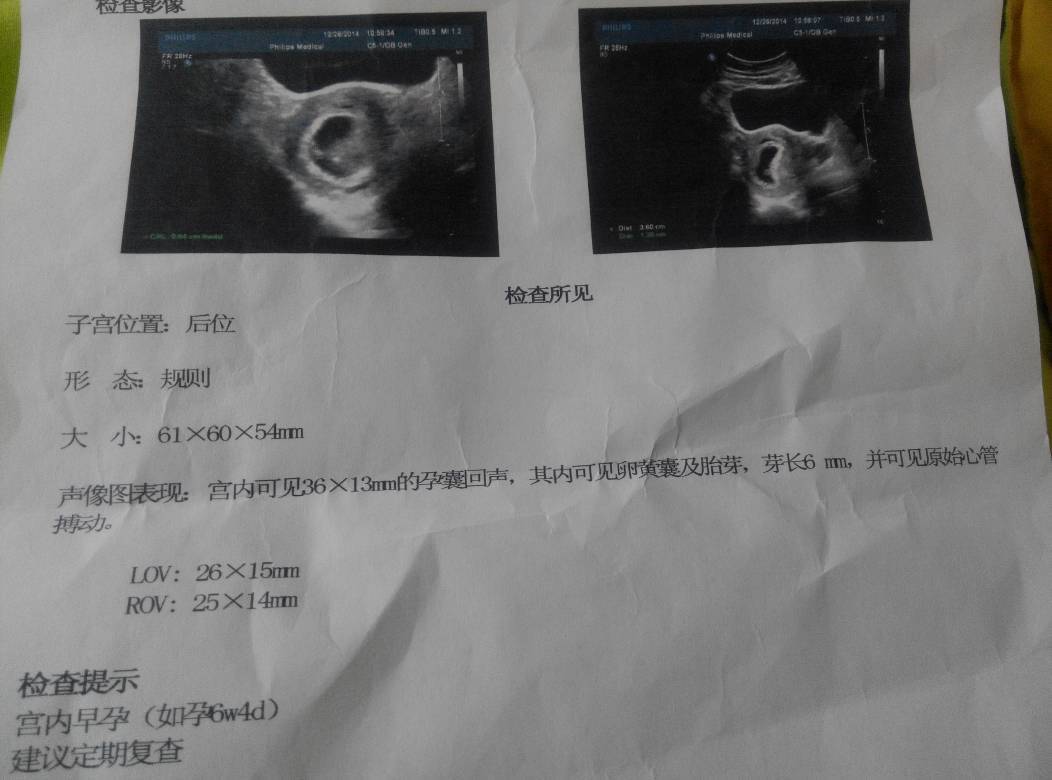

网上都说看比超单子知道男孩女孩,我也想知道,我这是第二胎,确实很期待,希望保佑帮忙看看我这个比超单子是男孩女孩?这是47天的比超单子,,求求求🙏🙏🙏🙏